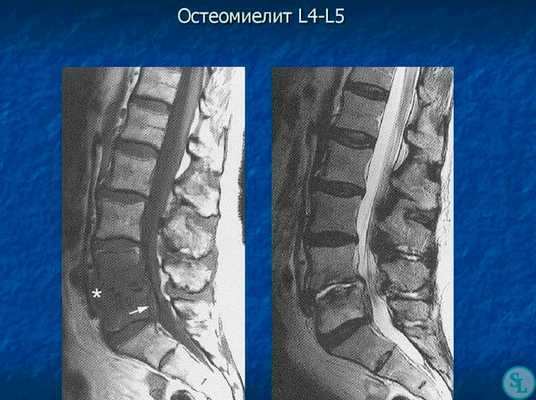

Инфекционные поражения позвоночника оценивают в зависимости от локализации очага, характера возбудителя (бактериальная или грибковая флора), пути заражения (прямая инокуляция возбудителя, контактное распространение из соседнего очага инфекции или гематогенное распространение), возраста пациента и его иммунного статуса. В условиях дисцита или спондилита все вышеописанные задачи нередко решаются без хирургического вмешательства. Предварительный диагноз ставится на основании данных лабораторного исследования, включающих увеличение скорости оседания эритроцитов (СОЭ) и уровня С-реактивного белка (С-РБ), и данных лучевых методов диагностики, включающих стандартную рентгенографию, компьютерную (КТ) и магнитно-резонансную (МРТ) томографию.

В диагностике заболеваний позвоночника большей популярностью пользуется магнитно-резонансная томография (или точнее «ядерно-магнитно-резонансная»), более безопасная и чувствительная, чем жесткое рентгеновское излучение. На снимках костные структуры получаются черными, но мягкие ткани, наполненные водой, передают все оттенки серого и белого цветов. Это позволяет обнаруживать мельчайшие объекты (узелковые образования, инфильтрации) и отслеживать динамику развития абсцесса.